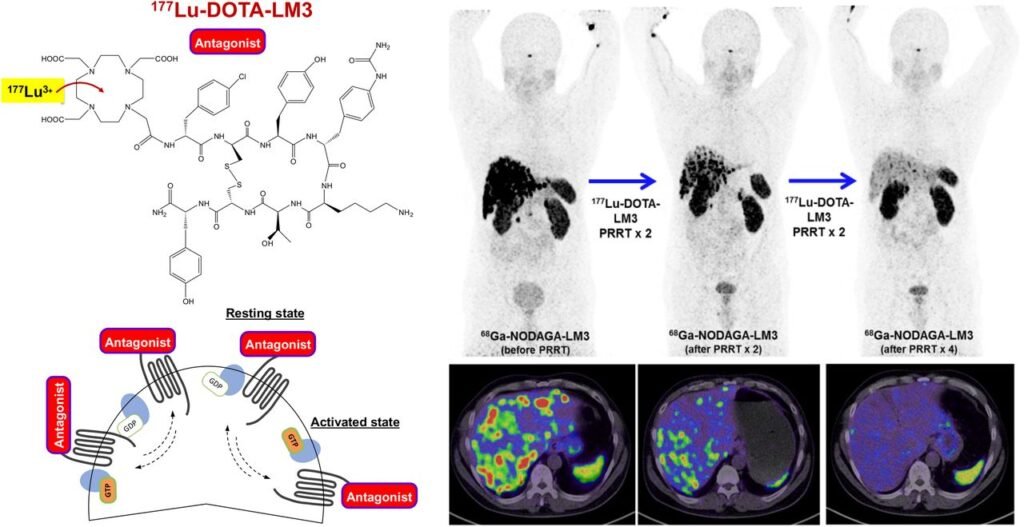

Advanced stage neuroendocrine tumors